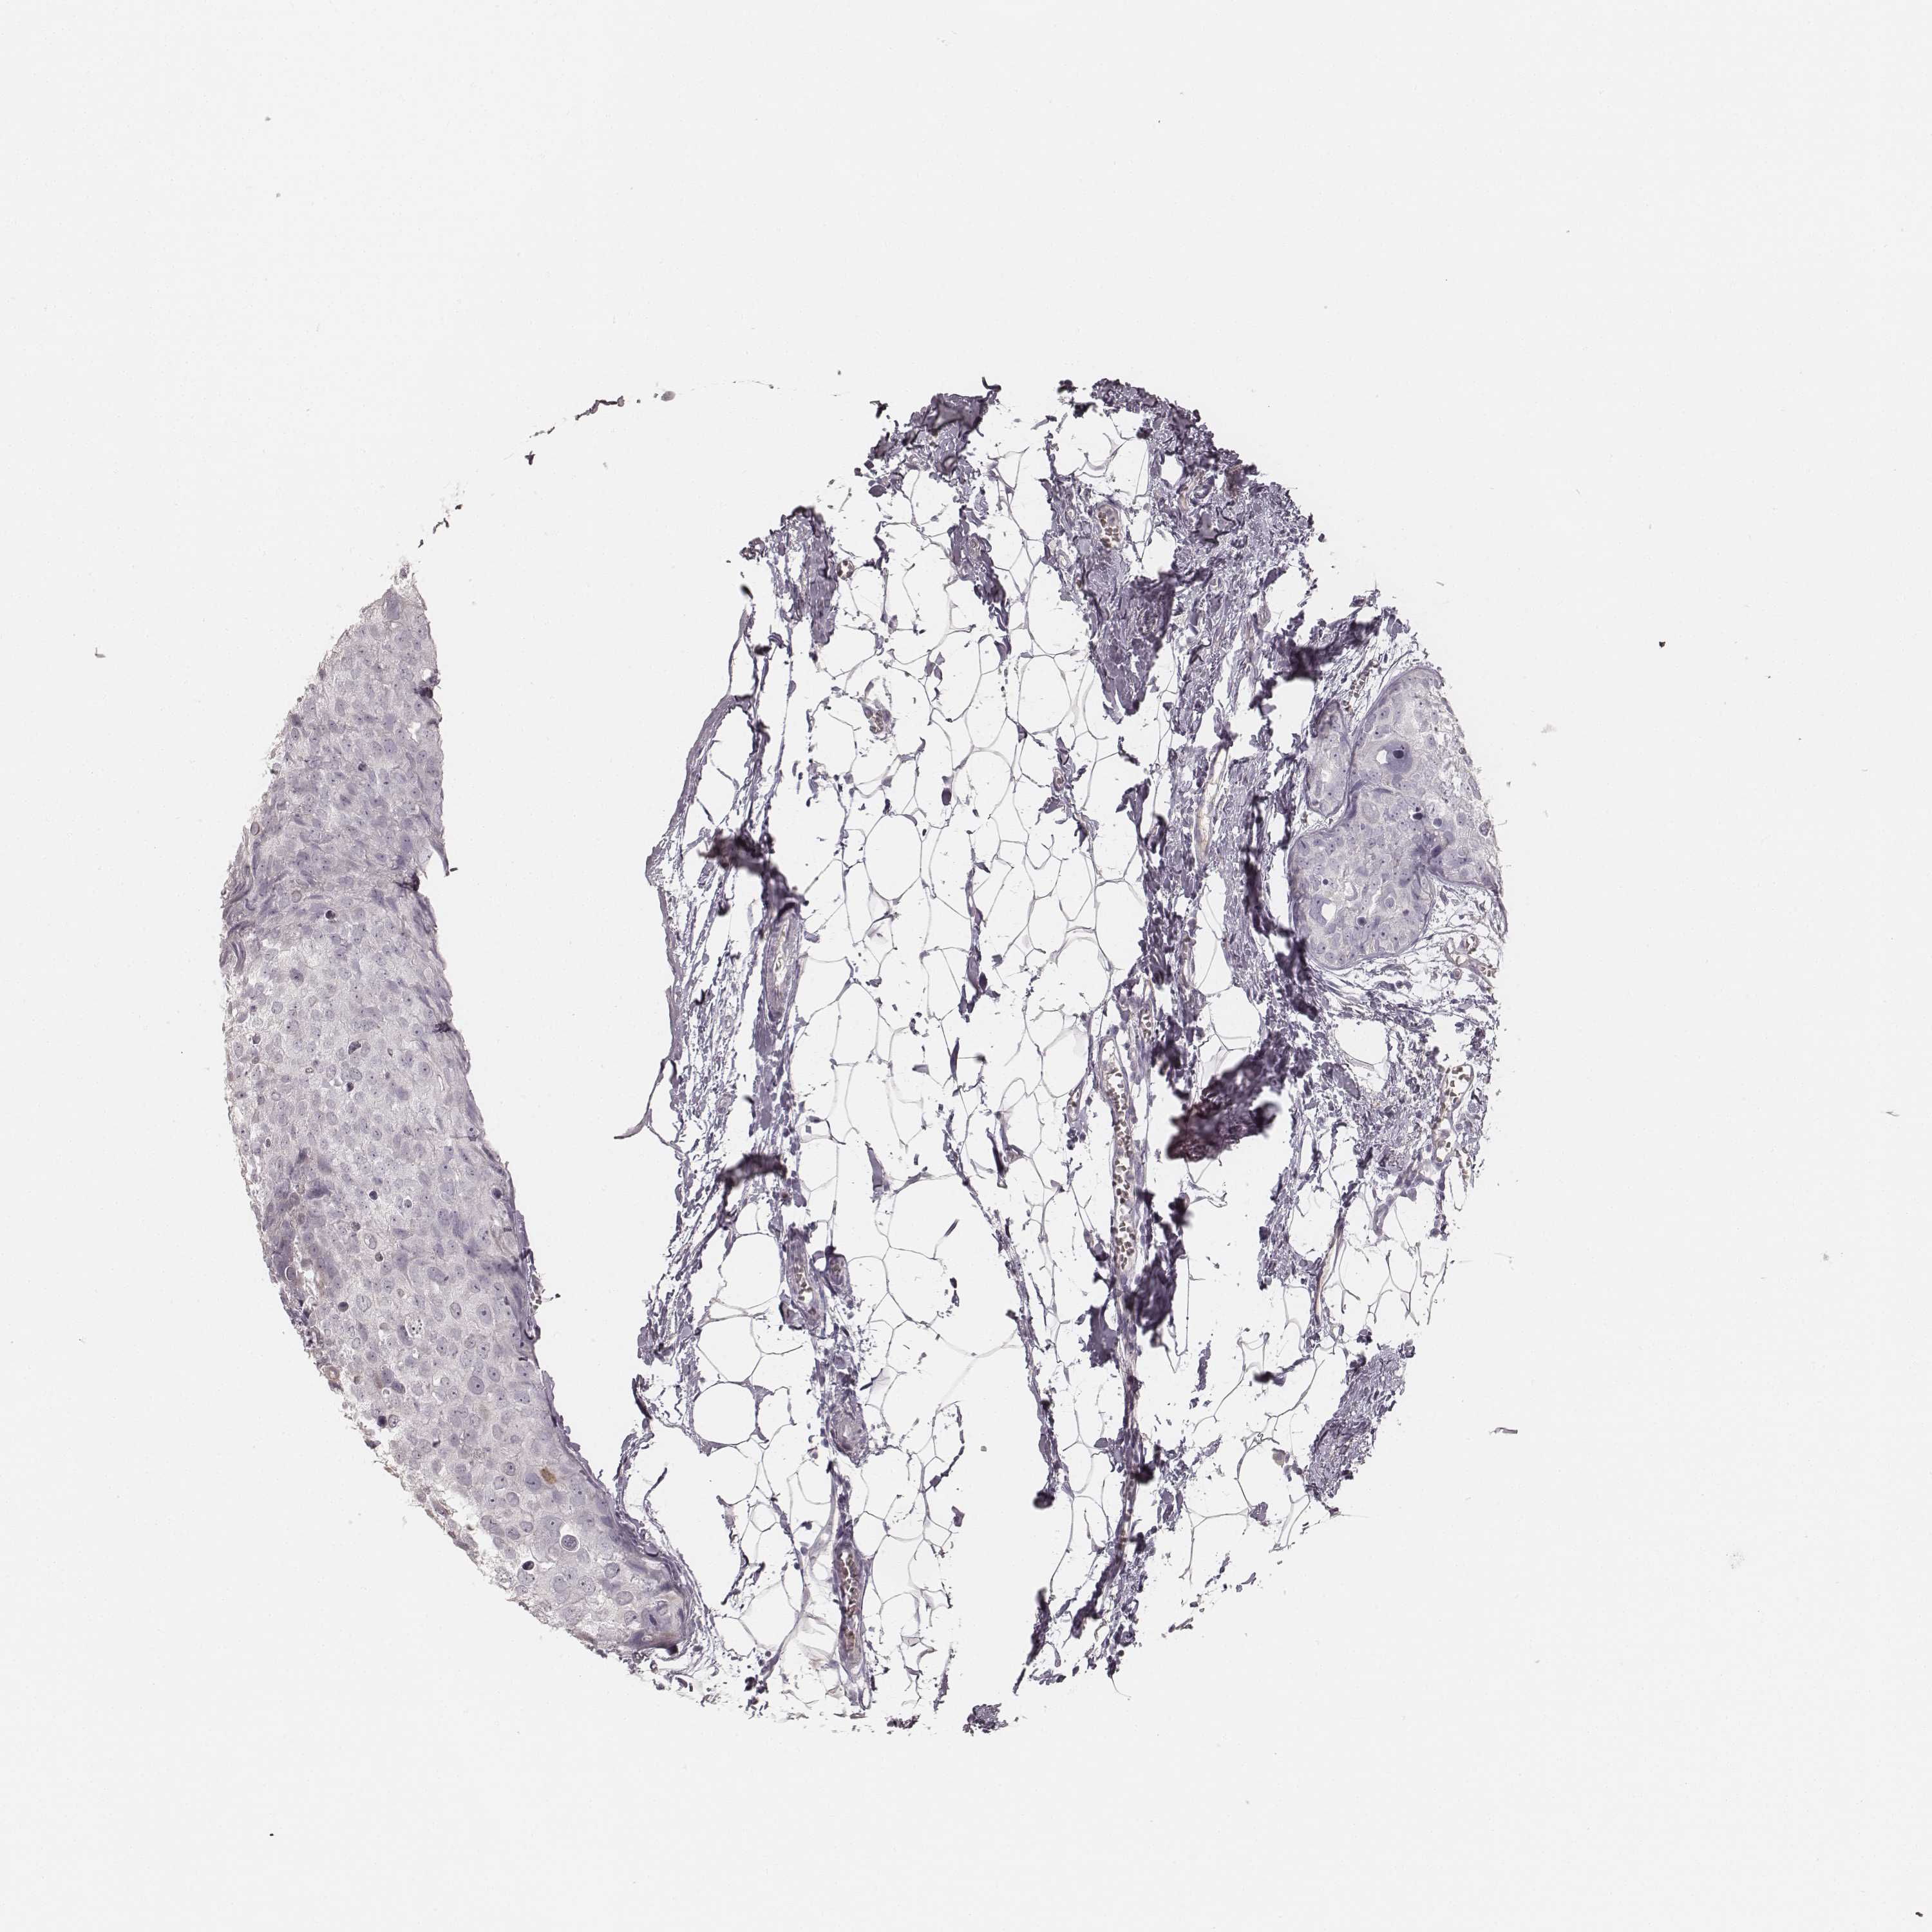

KRT31

CANCER BREAST CANCER Show tissue menu